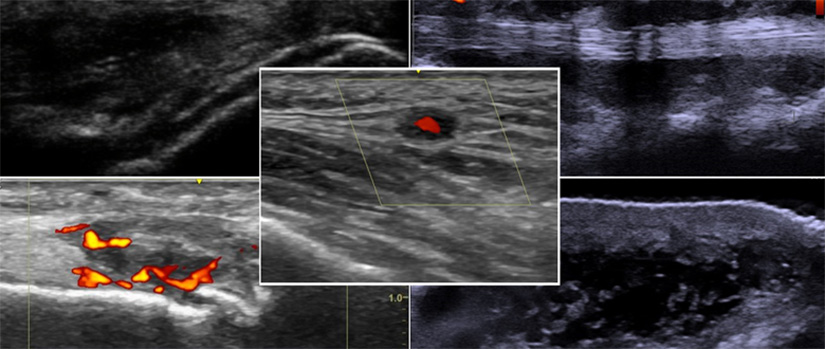

As a rotating student, resident, or fellow, you will be involved in the diagnosis and treatment of patients with rheumatic and musculoskeletal disorders. While rotating, you will learn how to think and approach patients like a rheumatologist. You will also participate in joint injections, musculoskeletal ultrasound, and bone densitometry assessment. Rotating students have successfully completed case reports, quality improvement, and database research projects based on their rheumatology experience.

Alvin Lee Day, MD, RhMSUS, CCD, FACP is a Clinical Assistant Professor and clinician-educator in the Division of Rheumatology. He is the Section Chief of Rheumatology at the Columbia VA Health Care System and the Medical Director of the Bone Health Clinic at Prisma Senior Specialty Care. Dr. Day’s academic interests include general rheumatology, musculoskeletal ultrasound, osteoporosis and metabolic bone disease, quality bone densitometry, and medical education. He is active in the Ultrasound School of North American Rheumatologists (USSONAR) and American College of Physicians. Dr. Day is currently a committee chair in the International Society for Clinical Densitometry (ISCD) and has served as a metabolic bone disease subject area expert for the American College of Rheumatology Continuing Assessment Review Evaluation (CARE) program.

Dr. Day received his medical degree from the University of South Carolina School of Medicine in Columbia, completed his residency in internal medicine at Prisma Health, also in Columbia, and completed a fellowship in rheumatology at UAB Hospital in Birmingham, Alabama. He has additional certifications in musculoskeletal ultrasound and clinical densitometry. Dr. Day is a co-author of the Manual of Musculoskeletal Ultrasound A Self-Study, Protocol-Based Approach.